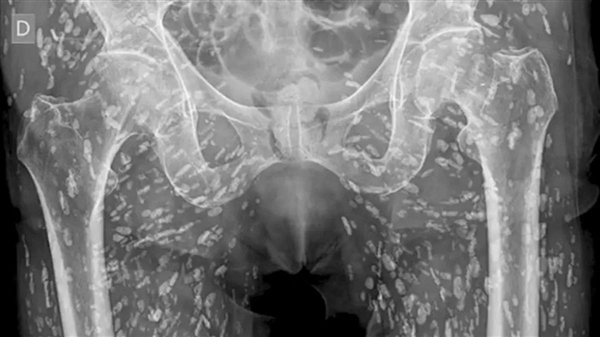

近日,美国佛罗里达大学急诊医学助理教授发布了一组令人震惊的X光片,他在社交媒体称其为见过最疯狂的X光片之一。

医生介绍,这名男子因食用未煮熟的猪肉,导致猪带绦虫的幼虫囊尾蚴在体内寄生,并在骨盆周围的软组织中留下大量虫卵。

这些虫卵在X光片上呈现为小白点,遍布男子下半身,数量之多,看得人头皮发麻。

囊尾蚴病可由猪带绦虫的幼虫囊尾蚴引起,可遍布全身,主要集中于臀部和腿部的肌肉和软组织,如果囊尾蚴游走到大脑并在那里停留,会导致头痛、意识混乱、癫痫发作甚至死亡等严重神经症状。